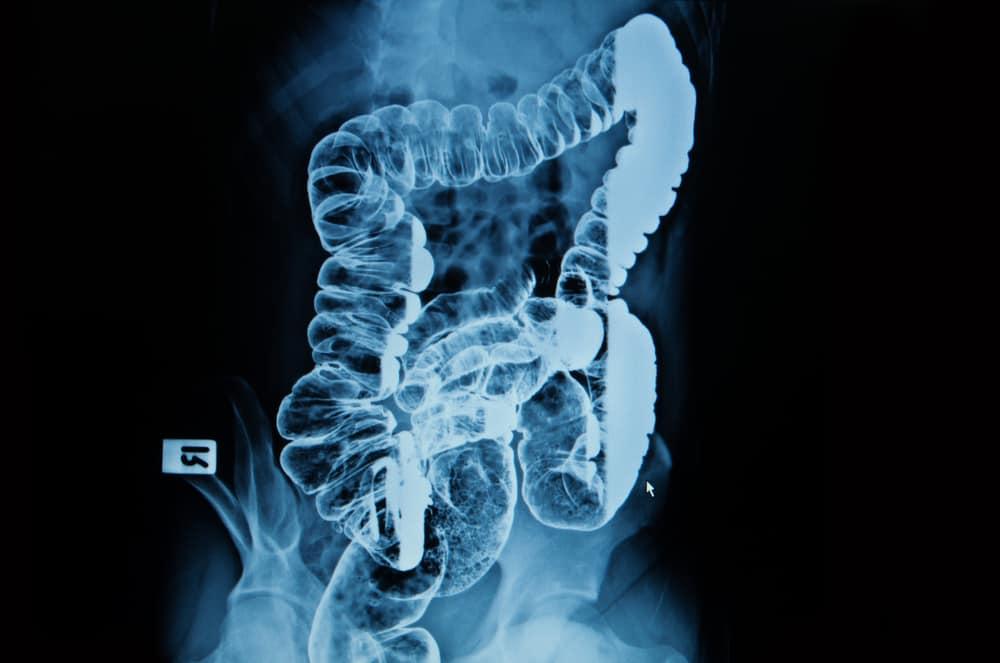

Barium enema adalah pemeriksaan sinar-X yang dilakukan pada saluran pencernaan bawah. Prosedur ini dilakukan untuk mendeteksi perubahan atau kelainan pada usus besar atau kolon. Barium enema dikenal juga dengan sebutan colon X-ray.

Prosedur barium enema melibatkan penuangan cairan barium sulfat ke dalam usus besar. Barium dapat menyerap sinar-X dan tampak berwarna putih dalam foto rontgen. Pola cairan akan menunjukkan apa penyebab masalah pada usus besar Anda.

Pemeriksaan akan dilakukan oleh seorang dokter spesialis bersama teknisi radiologi. Dokter kemudian melakukan pemeriksaan sinar-X untuk memastikan usus besar Anda benar-benar kosong.

Setelah itu, dokter atau teknisi akan memasukkan sebuah tabung enema yang telah diberi pelumas ke dalam rektum Anda. Tabung ini juga terhubung dengan kantong barium yang berfungsi mengirimkan cairan barium ke dalam usus besar.

Tabung pengirim barium memiliki sebuah balon kecil pada ujungnya. Saat ditempatkan dekat jalan masuk rektum, balon inilah yang akan menjaga barium tetap berada dalam tubuh Anda. Pada kasus tertentu, tabung ini juga berfungsi untuk mengirimkan udara.

Ketika rektum diisi oleh barium, Anda mungkin akan merasakan kram atau keinginan untuk buang air besar. Cobalah untuk menahannya dengan menjaga tubuh tetap rileks serta bernapas secara teratur.

Anda mungkin juga akan diminta menahan napas atau mengubah posisi sesekali. Ini dilakukan agar seluruh bagian usus besar terlapisi oleh barium sehingga bisa diamati dari berbagai sudut. Seluruh prosedur biasanya berlangsung selama 30 – 60 menit.